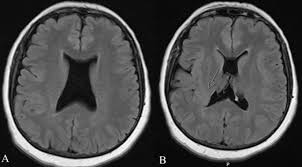

Huntington’s disease

atrophy of caudate head causes enlargement of frontal horns